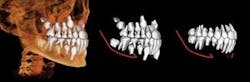

All CBCT manufacturers include OEM (Original Equipment Manufacturer) software with their machines. This software varies with the specific units, but generally includes a method of viewing the scan in an interactive frontal, sagittal, and coronal mode known as Multi-Planer Reconstruction (MPR). Each scan is reviewed first by browsing through the cross sections in all three planes and noting any findings, with particular attention paid to the diagnostic condition of interest (Figure 1).

Specialized orthogonal cross sections, such as panoramic planings, are performed to elicit a more directed view of areas of interest. The Hounsfield density measures the relative density of the involved structures and offers insight into the nature of the lesion. Most OEM software includes a 3-D viewer which can be applied to the scan to observe the volume of the target and its juxtaposition to other structures. Measuring tools in the software enable precise measurements in both the 2-D and 3-D images. The 3-D images can be cropped to decrease superimposition of adjacent structures — surface rendered to view skin and airway volume — all of which can be rotated for viewing at any angles. Most OEM packages have a function which displays corrected tomographic AP and coronal slices through the temporomandibular joints.